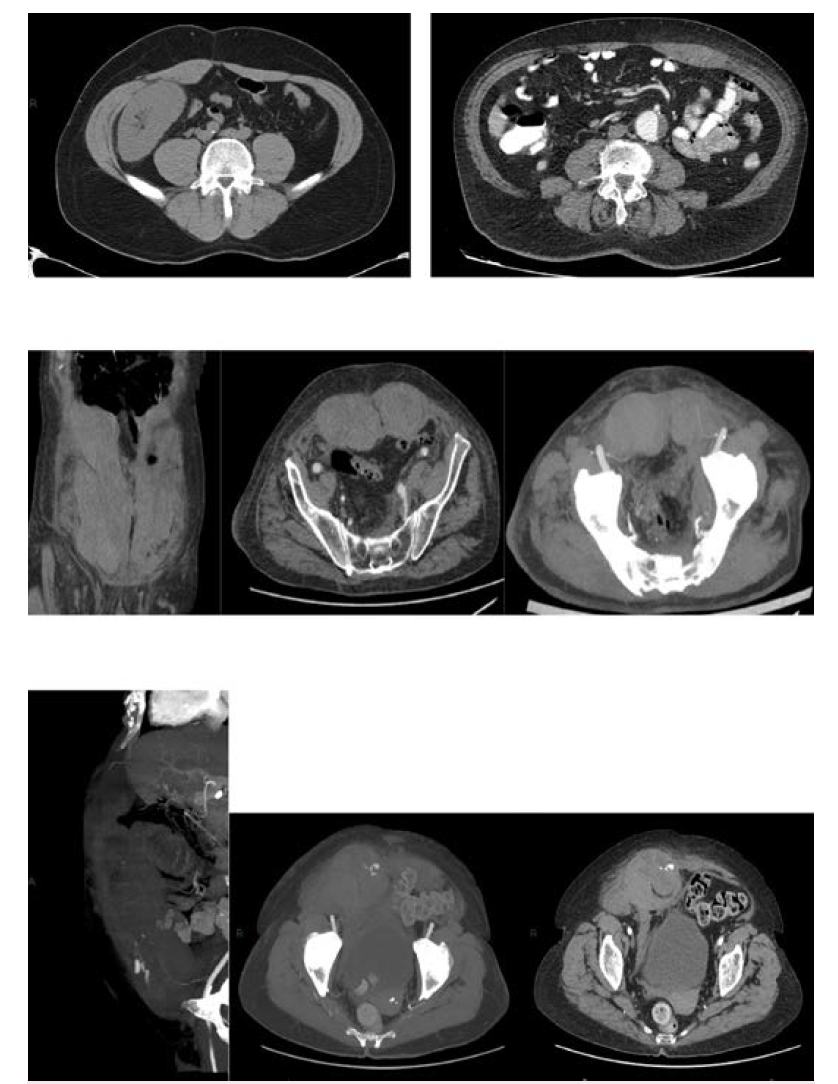

On the other hand, intravenous fluid resuscitation should be started in hemodynamically unstable patients. Red blood cell (RBC) transfusion depends on the hemodynamic status and presence of comorbid conditions.6 In an acutely hemorrhaging patient, transfusions should not be delayed awaiting laboratory tests. In addition, those patients who become hemodynamically stable with fluid resuscitation are managed as stable patients (transfuse if hemoglobin is <7g/dL).10 CT angiography must be performed as soon as possible. CT can help classify RSH according to the Berná classification as well as show evidence of active blood extravasation. The Berná grading system classifies RSH into 3 types: Type I, intramuscular and unilateral hematoma without hemodynamic compromise; Type II, unilateral or bilateral hematoma with blood between muscle and transversalis fascia, with a possible decrease in hematocrit; and Type III, hematoma associated with hemodynamic instability and with blood extending to the peritoneum and prevesical space6 (Figure 2). Active extravasation on CT angiography and a hematoma volume of >1000 mL to 1300 mL have been previously identified as predictors of conservative treatment failure.6,11 Therefore, the presence of active hemorrhage on CT angiography and/or hematoma (Type III) should promptly trigger endovascular arterial embolization or surgery. Historically, surgical ligation of the bleeding epigastric vessels was the treatment for uncontrolled RSH. However, it is well known that this technique is severely limited by the difficulties in localizing and ligating the bleeding vessel within the hematoma. Open surgery or guided drainage of RSH should be avoided when possible because it can diminish the potential tamponade effect of the rectus sheath.12 In line with this, surgery must be reserved for draining infected RSH and for controlling the bleeding in those health centers without hemodynamic and interventionist units. Selective arterial embolization, on the other hand, has been accepted as an effective and safe method for treating acute bleeding in patients with RSH.13 (Figure 3). Diamantopoulos et al reported 95.2% and 95% technical and clinical success, respectively, without rebleeding after epigastric artery embolization.14 Similarly, in a study by Contrella et al, the procedure only had to be repeated in 3 of the 32 patients who underwent endovascular embolization. In addition, no patient underwent surgery for RSH.6